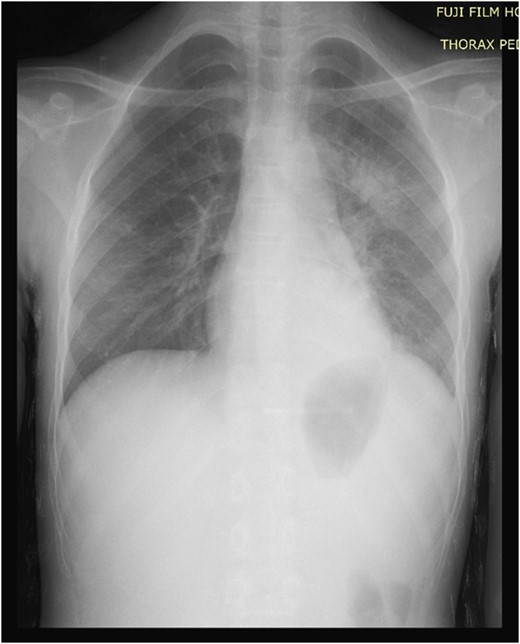

A 13-year-old female child was presented to the pediatric emergency unit with a painful swelling of the posterior left chest wall during the last 3 months. The patient was febrile without weight loss. She had a history of cutaneous mycosis for 2 years. The physical examination revealed a child in good general condition, febrile (axillary temperature was 38.2°C) and a painful swelling of the left posterior chest wall of ~6 × 4 cm2 (Fig. 1). The laboratory studies found a hemoglobin and hematocrit level of 10.5 g/dL and 34.4%, respectively, and a white blood cell count (WBC) of 15.210/μL with 80% neutrophils. Inflammatory indices such as erythrocyte sedimentation rate and C-reactive protein were greatly increased, with a level of 50 mm/h and 111 mg/L, respectively. The chest and the abdominal radiographs were found to be normal (Fig 2). The ultrasound showed an echogenic collection of the posterior chest wall of ~5 cm × 5 cm. A computed tomography (CT) scan of the chest with intravenous (IV) contrast showed a 6-3-5 cm pus collection of the posterior costovertebral region consistent with an osteomyelitis of the 10th, 11th, 12th ribs and soft tissue collection (Fig. 3). The abscess was incised and drained. A rib biopsy and a cytological examination of the pus were performed. Postoperatively the abscess was drained by a chest tube for two days before being removed. Postoperative antibiotic therapy with ceftriaxone, gentamicin and metronidazole was initiated. The pus culture was negative. Mantoux test and HIV test were negative. The histological examination of the rib biopsy disclosed a diagnosis of acute non-specific rib osteomyelitis. The patient was discharged after 2 weeks from hospital and the injection antibiotics were switched to oral administration (amoxicillin-acid clavulanic 80 mg/kg/day) for 6 supplementary weeks. The patient remains asymptomatic 6 months postoperatively.